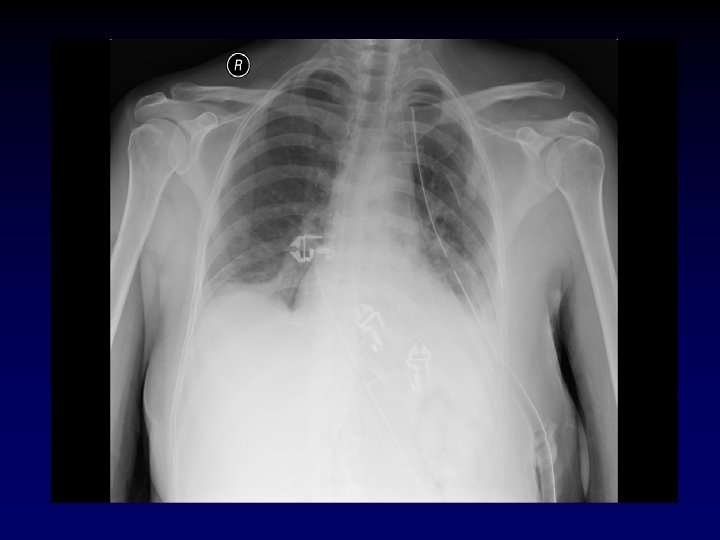

Case Presentation • 25 year old male presents s/p single stab wound to the left chest. He clearly smells of alcohol and is lethargic – responding only to painful stimuli. Field vitals are P 150, BP 80/palp, Resp 35. • What’s the plan? ?

Case Presentation • As you are screaming “a knife, my kingdom for a knife, ” your colleague successfully intubates with return of end-tidal CO 2. • The chest is auscultated with good breath sounds heard on the right, and no breath sounds on the left. • Now what?

Tube Thoracostomy • Indications: − Hemothorax/Pleural effusion − Pneumothorax − Note for tension pneumothorax first tx should be 14 or 16 guage angiocath in 2 nd intercostal space in midclavicular line. • Anatomy: • 5 th intercostal space in the anterior axillary line (at the level of the nipple). • Measure tube from insertion site to apex of lung.